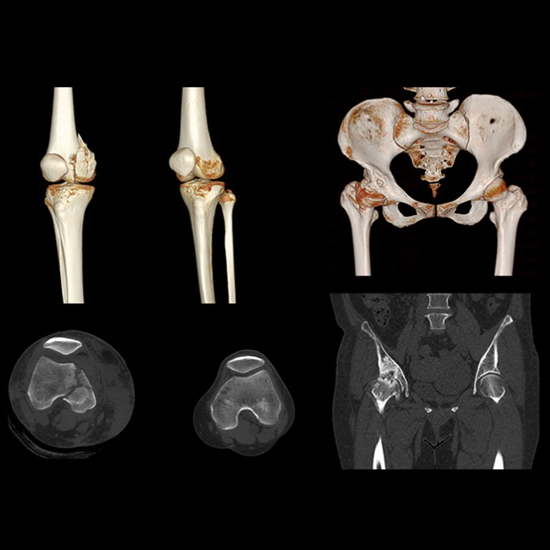

Anatom 64 Clarity, kardiyak görüntülemede giriş seviyesindeki rakiplerine oranla daha düşük doz ile daha yüksek kaliteli görüntüler sunan teknolojik donanımlara sahip 64 kesit bir bilgisayarlı tomografi sistemidir.

Yüksek zamansal çözünürlük sunarak kullanıcı deneyimini iyileştiren Anatom 64 Clarity, aynı zamanda 5.3 MHU'luk tüpü sayesinde 120 saniyeye kadar devamlı çekim imkanı sunar ve tüm gün çekimlerde herhangi bir sorun yaşanmamasına olanak tanır.

Görüntü bozulmalarını engelleyecek yazılımlara sahip olan Anatom 64 Clarity, farklı klinik ihtiyaçlara uyum sağlayabilmesi için dijital ve mekanik eğim ayarlarına sahiptir ve gerçek zamanlı çarpışma önleme sistemleriyle hasta güvenliğini de sağlar.